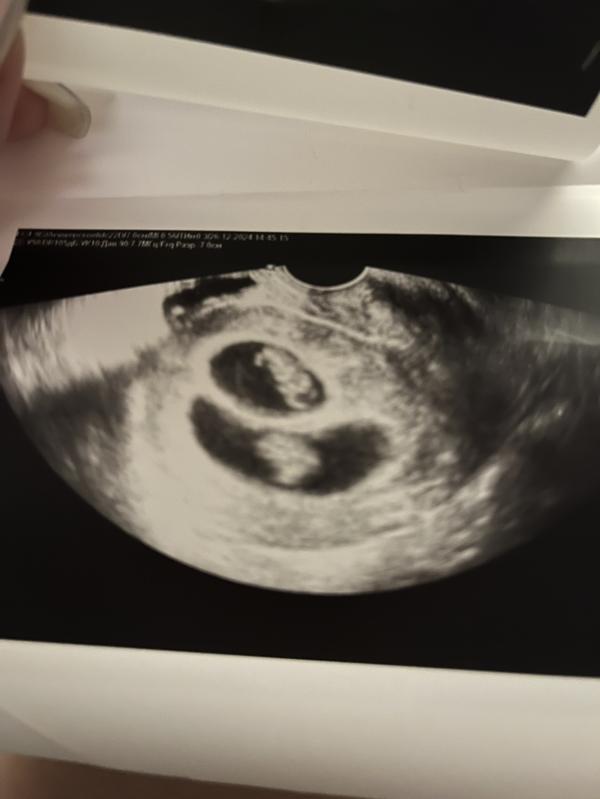

Пошла на узи, рано, пока ещё ничего не видно. Врач сказал придти через пару дней. Я пришла в назначенный день, она вводит датчик и говорит: «Двойня».

Дихориальная диамниотическая двойня.

Последнее фото самое интересное, лежат как в плацкарте😄🥹😍